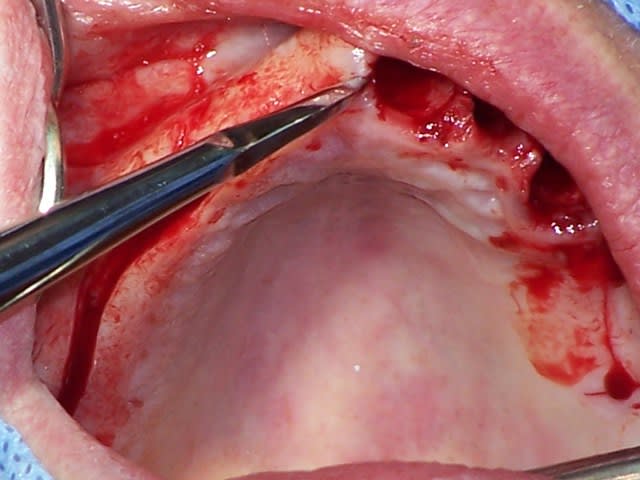

Eu pratiquant une mise en charge légèrement ou différée tu perds tous les avantages de la mise en charge immédiate. Le protocole de mise en charge immédiate POSITDENTAL est maintenant éprouvé, inévitablement il requiert une bonne maîtrise de l’implantologie. La passivité et précision du bridge se faont lors de la mise en place.

Vidéo d'une mise en charge immédiate: